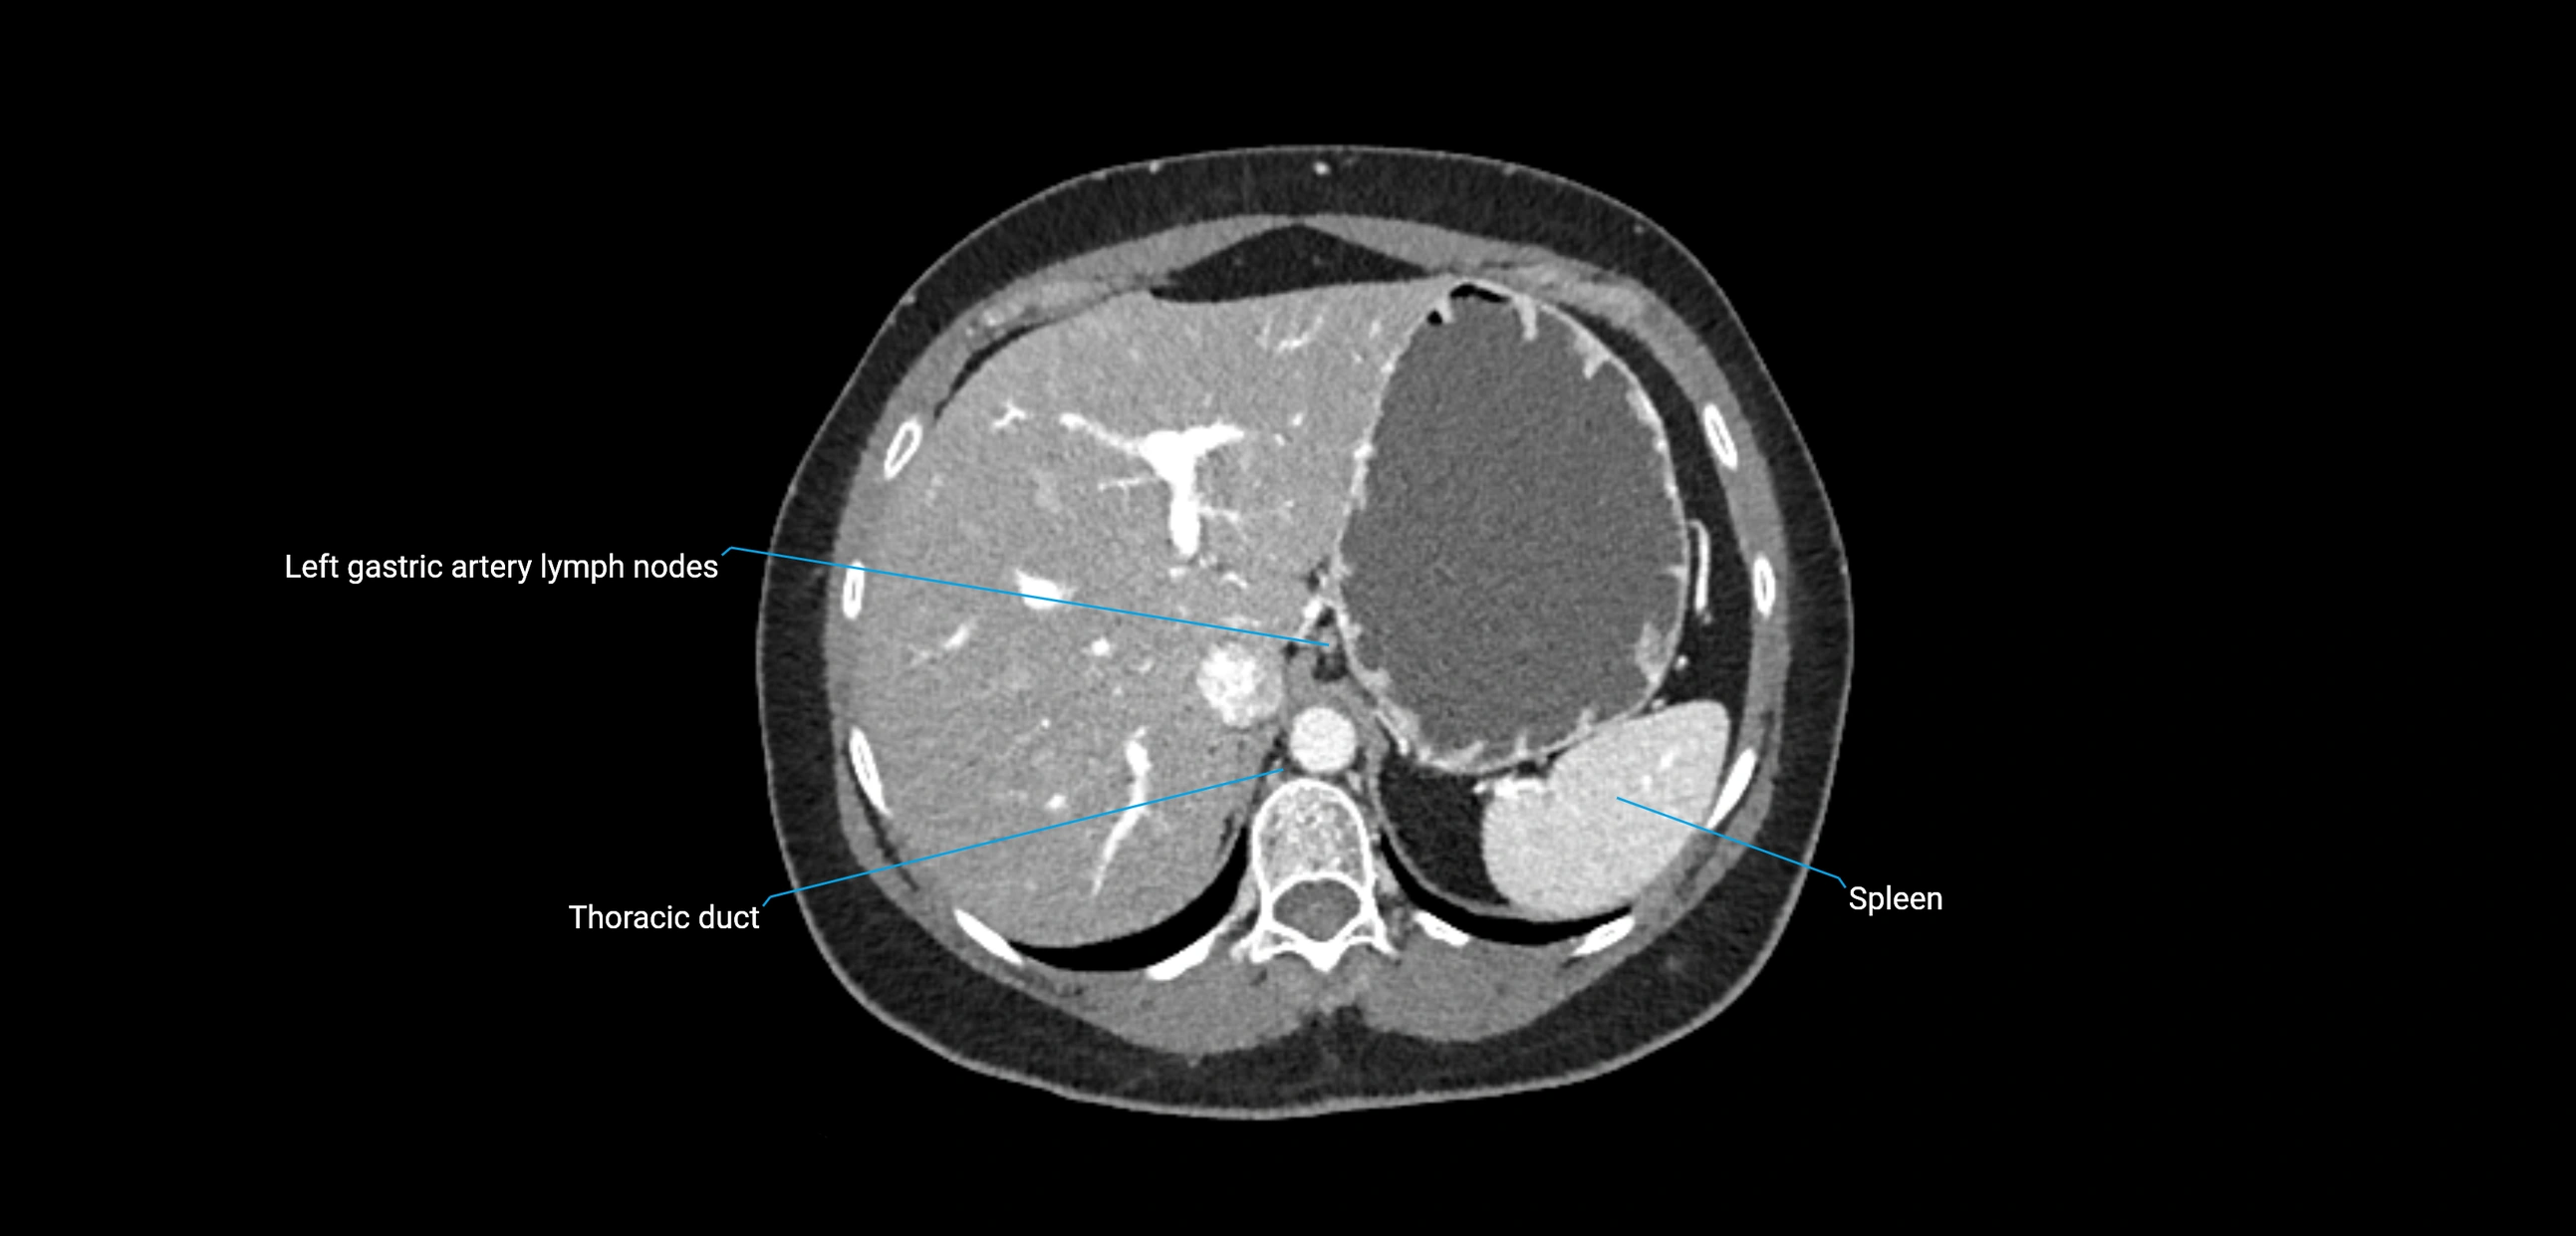

CT Appearance

CT Pre-Contrast:

• Nodes appear as soft-tissue density nodules adjacent to the aorta and IVC

• Calcification may be seen in chronic infections (e.g., tuberculosis)

CT Post-Contrast:

• Normal nodes enhance homogeneously

• Malignant nodes may show heterogeneous enhancement, central necrosis, or conglomerate formation

• Size >1 cm short axis is suspicious, though morphology and distribution are equally important